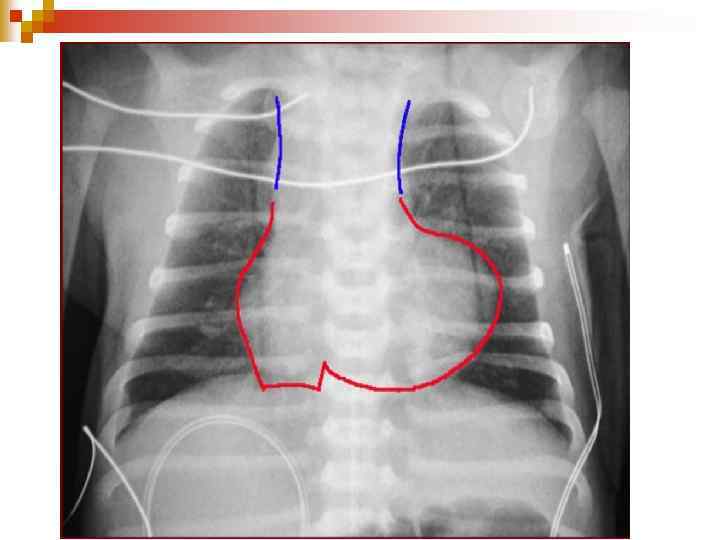

Діагностика ЕКГ: ознаки гіпертрофії ЛШ або обох шлуночків, при склеротичній формі гіпертензії – тільки правого; n Ехо-КГ: візуалізація самого дефекту; n Рентгенологічно: Ш посилення та повнокрів’я легеневого малюнку, розширення коренів легень, збільшення розмірів серця; Ш У період декомпенсації: збіднення легеневого малюнку. n

Диагностика При рентгенологическом исследовании органов грудной клетки описывают форму сердца и состояние легочного рисунка, определяют размер кардиоторакального индекса (КТИ). Все эти показатели имеют свои особенности при разных степенях лёгочной гипертензии. В первой, гиперволемической стадии, выявляется сглаженность талии и погруженность верхушки сердца в диафрагму, увеличение КТИ. Со стороны легочного рисунка отмечается его усиление, нечеткость, размытость. Крайней степенью гиперволемии в лёгких является отёк лёгких. В переходной стадии лёгочной гипертензии отмечается нормализация лёгочного рисунка, некоторая стабилизация размеров КТИ. Для склеротической стадии лёгочной гипертензии характерно значительное увеличение размеров сердца, причем в основном за счёт правых отделов, увеличение правого предсердия (формирование прямого атрио-вазального угла), выбухание дуги лёгочной артерии (индекс Мура более 50%), приподнятость верхушки сердца, которая образует с диафрагмой острый угол. Со стороны лёгочного рисунка часто описывается симптом «обрубленного дерева» : яркие, чёткие, увеличенные корни, на фоне которых лёгочный рисунок прослеживается только до определённого уровня. На периферии имеет место признаки эмфиземы. Грудная клетка имеет вздутую форму, ход ребер горизонтальный, диафрагма уплощена, стоит низко.